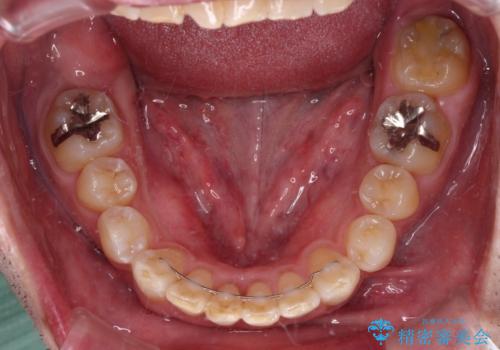

矯正治療後にはオーダーメイドタイプのオールセラミッククラウンを装着し、自然な口元に仕上がりました。

通常では速やかにオールセラミッククラウンにて補綴治療を行うのですが、デコボコしている歯列も気になっていたため、事前に矯正治療を行うこととしました。

上顎歯列の叢生が著しかったため、上顎左右第一小臼歯2本を抜歯し、目立たないワイヤー装置にて治療を進めることとしました。